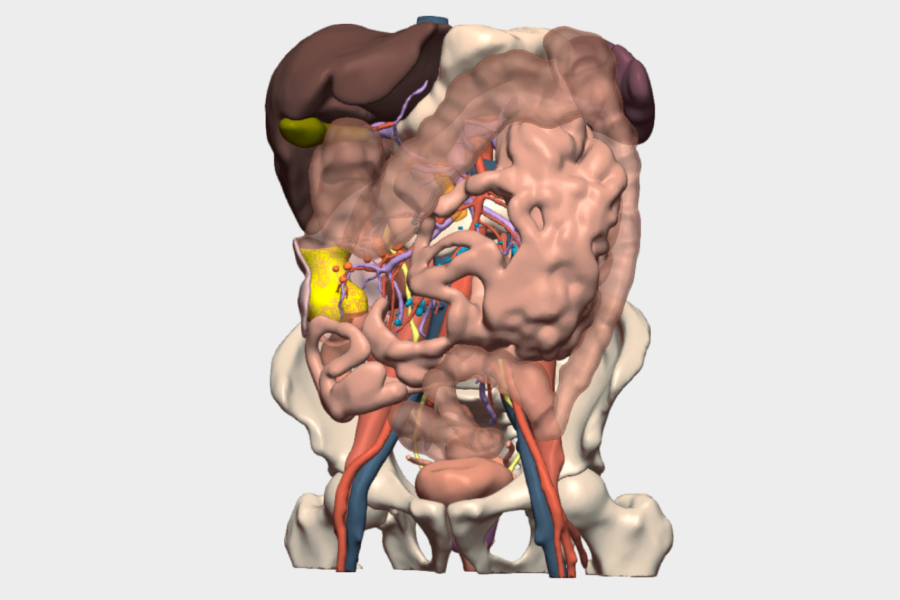

En el protocolo de prehabilitación (GRAMGEA) se detecta déficit leve de Factor VII, valorado por Hematología, indicándose vitamina K preoperatoria. El paciente pesa 80 kg, mide 177 cm (IMC 25) y es clasificado como ASA I. Se administra bolo de hierro IV (1500 mg) y se indican ejercicios de fisioterapia respiratoria. En quirófano se dispone de un modelo 3D virtual personalizado, basado en las pruebas de imagen del paciente, visible y navegable durante toda la intervención, lo que permite una cirugía dirigida, precisa y personalizada. Se localiza la tumoración en el ángulo esplénico, con gran induración, neovascularización e invaginación colocólica, hallazgos correlacionados con el modelo 3D. Se identifica la vena mesentérica 2 inferior (VMI) y se realiza disección mesocólica respetando cola de páncreas, bazo y fascia de Toldt izquierda.

Gracias a la reconstrucción 3D, se identifican dos arterias cólicas izquierdas procedentes de la Aorta, además del tronco de la cólica izquierda de la Arteria Mesenterica Inferior (AMI) permitiendo una ligadura vascular selectiva, respetando la arteria mesentérica inferior y la cólica izquierda más distal que no interesa la tumoración ni el margen de resección de seguridad, optimizando de esa manera la colectomía segmentaria del ángulo esplénico. Se realiza además sección de la rama izquierda de la cólica media.

La reconstrucción 3D fue especialmente relevante en la identificación y comprensión de la anatomía vascular mesentérica, donde se objetivó la presencia de dos arterias cólicas izquierdas, una variante anatómica con impacto directo en la estrategia quirúrgica.

Asimismo, permitió anticipar la localización exacta del tumor en el ángulo esplénico, su relación con la invaginación colocólica y con estructuras críticas como el páncreas y el bazo, reduciendo la incertidumbre intraoperatoria y aumentando la seguridad del procedimiento

El modelo 3D de CELLA permitió una visualización interactiva y navegable en tiempo real, con segmentación detallada de vasos, colon, mesocolon y órganos adyacentes. La posibilidad de rotar, aislar estructuras y correlacionar la imagen virtual con la anatomía real durante la cirugía fue clave para la identificación vascular precisa y la planificación de una resección segura. Esta funcionalidad aportó un valor diferencial al facilitar una cirugía más predecible, personalizada y eficiente, con mínima pérdida hemática y excelente evolución postoperatoria.